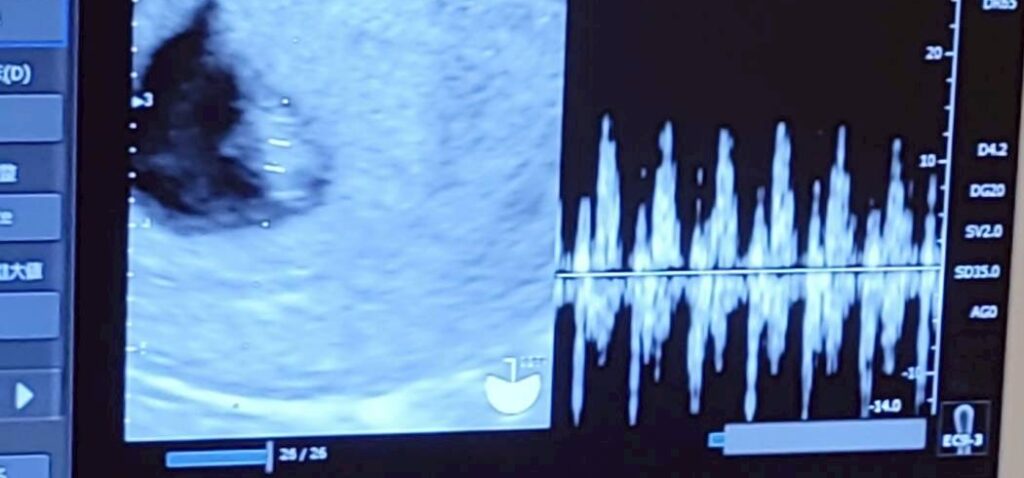

経膣エコーで妊娠の確認

あとは経膣エコーで正常な妊娠かどうかチェックしてもらいます。

6週目なので心拍も確認できれば尚良し!

それでは内診台に乗って、経膣エコーでいざ確認!

すぐに私の子宮内に見慣れない黒い塊と真ん中に白い影が確認できました!

正常な妊娠ですーーー!!😭

しかも心拍も確認できました!

こんな豆粒みたいなのに、もう心臓が動いているんですね。

そうして初めてのエコー写真をもらって、次は2週間後にまた胎児の様子を見るため、予約を取りました。(次の予約が“心拍の確認“になっていて、今日心拍確認したのにまた確認するんだな〜と呑気に思っておりましたが、ちゃんと確認すべきでした😣)